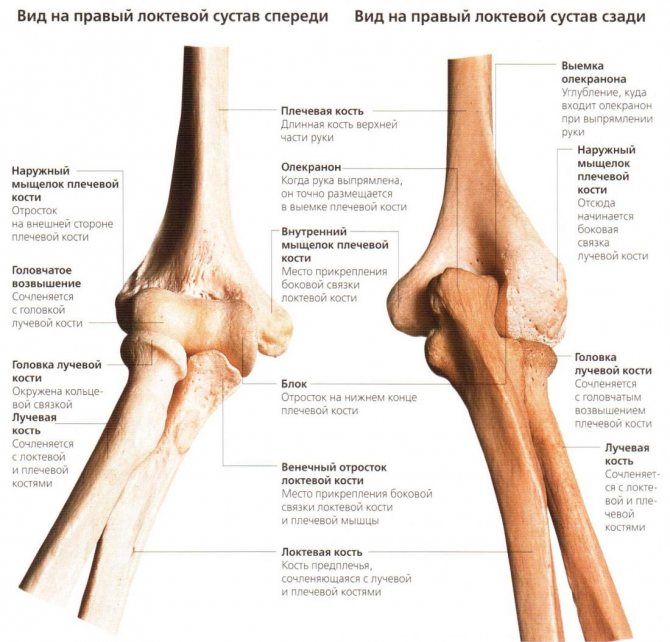

Чтобы больше узнать о локтевом суставе, сначала следует ознакомиться с его анатомией. И только потом можно говорить о функции, ведь она определяется структурой. Сустав объединяет несколько костей: плечевую, локтевую и лучевую. Они являются структурной основой для верхней конечности. У локтя довольно сложное строение, поскольку под одной капсулой заключаются сразу три сустава:

- Плечелоктевой.

- Плечелучевой.

- Лучелоктевой (проксимальный).

Следовательно, строение локтевого сустава нужно рассматривать как совокупность отдельных сочленений, входящих в его состав. А понять анатомию помогут изображения этой области.

Плечелоктевой

Плечевая кость на дистальном конце (т. е. удаленном от срединной оси тела) имеет хрящевую поверхность в виде блока. Именно к ней прилегает специальная вырезка на верхней части локтевой кости. Она охватывает вышеуказанный блок снизу и сзади. Так формируется плечелоктевой сустав – самое крупное сочленение из рассматриваемых.

Выше хрящевой поверхности плеча находятся венечная и локтевая ямки. Сюда упираются соответствующие отростки, когда предплечье достигает положения крайнего сгибания и разгибания, что ограничивает двигательную амплитуду.

Плечелоктевой сустав имеет блоковидную форму и винтообразное строение. Он обеспечивает сгибание и разгибание предплечья на угол до 140 градусов.

Плечелучевой

Латеральнее, т. е. снаружи от плечелоктевого сочленения находится другой сустав – плечелучевой. Он имеет шаровидную форму и образован головкой мыщелка плеча и тем концом лучевой кости, который расположен ближе к центру тела (проксимальным). В указанном суставе, как и в плечелоктевом, производятся движения вдоль сагиттальной оси – сгибание и разгибание. По сути они как бы дополняют друг друга, поскольку кости предплечья соединены между собой. Но кроме этого, в плечелучевом соединении происходит еще и вращение.

Лучелоктевой

И последнее соединение, на которое нужно обратить внимание – это проксимальный лучелоктевой сустав. По своей форме он цилиндрический и образован головкой луча и вырезкой на боковой поверхности верхнего конца локтевой кости. В нем возможны движения вдоль вертикальной оси – ротация: наружная (супинация) и внутренняя (пронация). Причем их амплитуда достигает 140, а в некоторых случаях и 180 градусов. Необходимо понимать, что одновременно функционирует и одноименный сустав, расположенный дистальнее. Вместе с проксимальным он составляет комбинированное сочленение.

Локтевой сустав — сочленение трёх костей: дистальной части плечевой кости (располагается дальше от туловища), проксимальной части локтевой кости и проксимальной части лучевой кости (располагаются ближе к туловищу).

Латинское название локтевого сустава — articulátio cúbiti, данный сустав представляет собой сочленение трёх костей: дистальной части плечевой кости (располагается дальше от туловища), проксимальной части локтевой кости и проксимальной части лучевой кости (располагаются ближе к туловищу).

Анатомическое строение локтевого сустава

Согласно анатомическому строению локтевой сустав можно отнести к сложным суставам, поскольку сочленение костей образует 3 простых сустава, объединенные в одну общую капсулу.

Плечевая кость — это типичная трубчатая кость. Тело кости верхнего отдела на поперечном сечении имеет округлую форму, а нижний отдел трехгранную.

Если говорить о нижнем конце (дистальном эпифизе) плечевой кости, то он образовывает мыщелок и обладает суставной поверхностью, которая сочленяет его с костями предплечья. Медиальная часть поверхности сустава, сочлененная с локтевой костью — это блок плечевой кости, латеральная часть, сочлененная с лучевой костью по своей форме шаровидная, ее называют головкой мыщелка плечевой кости. Над блоком плечевой кости спереди и сзади расположены специальные ямки, в которые при разгибании и сгибании предплечья входит венечный (он расположен спереди) и локтевой (располагается сзади) отросток локтевой кости. Такие ямки имеют свое название, спереди — венечная ямка, а сзади — ямка локтевого отростка.

С обеих сторон нижнего конца плечевой кости располагаются латеральный и медиальный надмыщелки, они легко прощупываются под кожей, особенно это касается медиального, ведь на его задней стороне расположена борозда локтевого нерва. Надмыщелки выполняют функцию для прикрепления мышц и связок. На задней части тела плечевой кости сверху вниз проходит борозда лучевого нерва.

Локтевая кость также обладает трехгранной формой. Верхний проксимальный участок кости имеет характерное утолщение, на котором спереди расположена блоковидная вырезка, которая необходима для сочленения с плечевой костью, латеральный край имеет лучевую вырезку, которая в свою очередь служит для сочленения с головкой лучевой кости. Ниже переднего отростка расположена бугристость локтевой кости, именно к ней прикрепляется плечевая мышца. Дистальный конец локтевой кости образует утолщение, его название — головка локтевой кости. На лучевой стороне дистального конца находится суставная поверхность. Она необходима для сочленения с лучевой костью. Локтевая кость на всем своем протяжении (от локтевого отростка до шиловидного) также легко ощущается под кожей. На верхней передней части кости расположены мышцы, в нижней части — сухожилия.

Лучевая кость характеризуется тем, что утолщение находится не на верхнем, а на нижнем конце. У верхнего конца имеется головка лучевой кости, которая обращена в сторону плечевой кости. По краю головки кости расположена суставная окружность, она необходима для сочленения с локтевой костью. Немного ниже головки у лучевой кости находится наиболее суженное место, оно называется шейкой лучевой кости. Немного ниже шейки расположена довольно выраженная бугристость, она является местом прикрепления сухожилий двуглавой мышцы плеча. Эпифиз (нижний конец) лучевой кости имеет запястную суставную поверхность, она сочленяет его с костями запястья. Снаружи эпифиза имеется латеральный шиловидный отросток, хорошо прощупываемый под кожей, а изнутри — локтевая вырезка, сочленяющая конец с головкой локтевой кости. Края локтевой и лучевой кости острые и обращены друг к другу, благодаря этому обеспечивается ограничение межкостного пространства, именно поэтому они называются межкостные края.